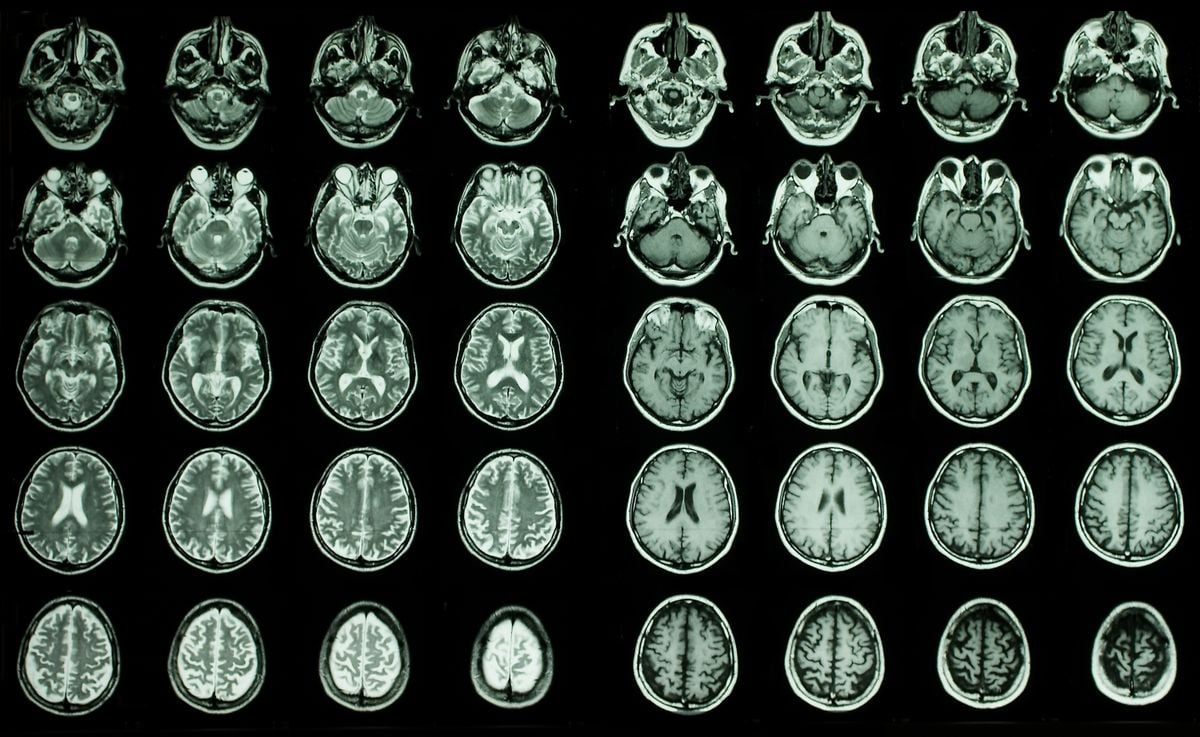

В статье, опубликованной в этом месяце в Природное старениегруппа ученых проанализировала почти 11 000 снимков мозга с помощью магнитно-резонансной томографии (МРТ) людей в возрасте от 45 до 82 лет, которые были включены в Биобанк Великобритании. Они использовали искусственный интеллект, чтобы определить «возраст мозга» по сканам на основе таких характеристик, как объем мозга и площадь поверхности — по сути, они предсказали, сколько лет человеку, основываясь на данных его мозга. Это число «возраста мозга» может отличаться от хронологического возраста человека и может пролить свет на когнитивное старение и риск нейродегенеративных заболеваний.

Затем исследователи оценили концентрацию 3000 белков в крови участников, чтобы определить, какие белки, доставленные в мозг через кровеносные сосуды, связаны с возрастом мозга. Они пришли к выводу, что 13 белков — восемь связаны с быстрым старением мозга и пять — с медленным старением — по-видимому, связаны с возрастом мозга. Сообщается, что количество некоторых белков, которые влияют на клеточный стресс и воспаление, увеличивается с возрастом, в то время как количество других, которые помогают в задачах поддержания, таких как регенерация клеток, сокращается. Живая наукаЭто Эмили Кук.